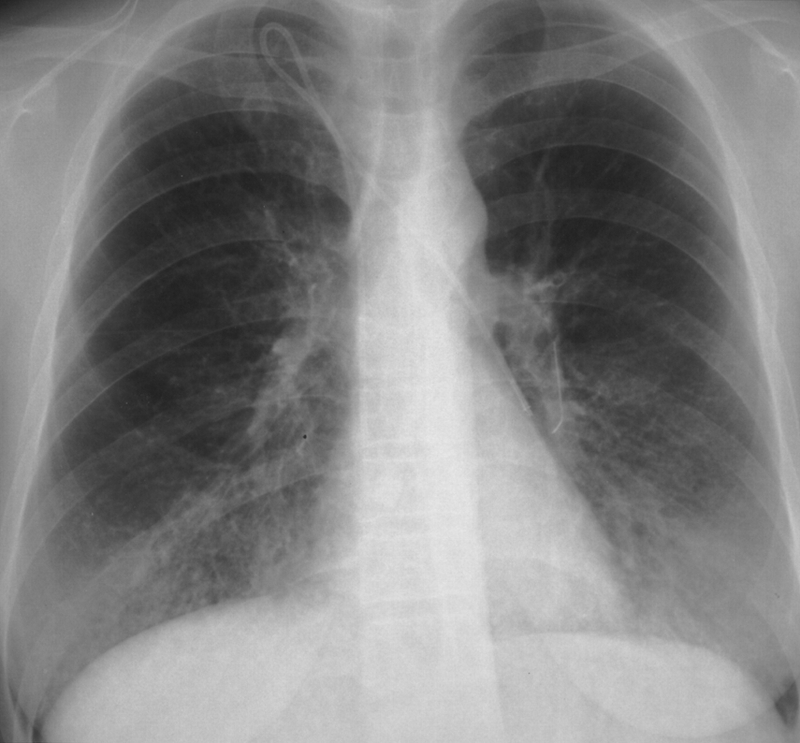

Cách chẩn đoán mức độ tổn thương của phổi thường là hình ảnh chụp Xquang và CT phổi có thể dùng thuốc cản quang hoặc không và chụp độ phân giải cao.

Bác sĩ sẽ dựa vào hình ảnh của phim để đưa ra chẩn đoán mức độ tổn thương tùy theo thể lao hoặc các giai đoạn của bệnh lao.

Theo chẩn đoán lâm sàng, các triệu chứng bất thường về chức năng hô hấp như thiếu oxy lên máu, giảm tối đa áp lực hít vào, hội chứng giới hạn với giảm sự khuếch tán khí CO2,... Khi chụp Xquang và CT, bác sĩ sẽ đưa ra chẩn đoán dựa trên hình ảnh những vết mờ ở đáy phổi, hình ảnh tổ ong và các dải mờ mở rộng.